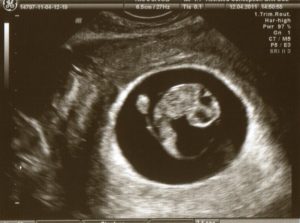

УЗИ

Размеры плода на восьмой неделе беременности соответствуют ягоде малины, но с каждым днем он становится похожим на человека. Поэтому, с помощью ультразвукового исследования у будущих родителей есть возможность понаблюдать за своим малышом и проверить его сердцебиение, которое делает 150 ударов в минуту.

Узи на 8 неделе беременности

Как правило, к этому сроку будущая мама уже знает о своем интересном положении и скорее всего уже прошла УЗИ. Повторные исследования на этом сроке проводятся лишь в случае крайней необходимости по медицинским показаниям или если процедура не была пройдена на предыдущих этапах.

Если пару недель назад наш малыш был похож формами на маленькую фасолинку или горошинку, то сейчас это уже человечек ,и от предыдущих сравнений остался разве что его крошечный размер.

Маленькие ручки и ножки уже пришли в движение, и Вы сможете увидеть их на экране монитора Сердцебиение плода намного чаще, чем у взрослого человека и достигает 150 ударов в минуту – это связано с тем, что его сердечко ускоренно гоняет кровь по крошечному тельцу.

Частота сердечного ритма — очень важный показатель, по значению которого врач может судить о нормальном формировании сердечнососудистой системы и о том, в достаточном ли количестве будущий малыш получает кислород.